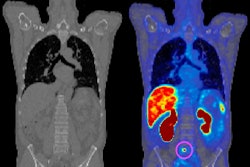

Initial preclinical data from a study on ATNM-400's performance will be presented at the American Association for Cancer Research (AACR) annual meeting being held between 25 and 30 April 25 in Chicago. This presentation will share results from in vitro and in vivo studies, including biodistribution imaging and efficacy analyses with various dose levels of ATNM-400.

Actinium is expecting additional data from Pluvicto-resistant prostate cancer models at the AACR meeting. Pluvicto (Lu-177-PSMA-617) is a PSMA-directed targeted radiotherapy that uses the beta-particle emitting radioisotope Lutetitium-177 (Lu-177) that is approved for patients with metastatic prostate cancer. ATNM-400 targets a different marker than PSMA that has been shown to be overexpressed in patients with prostate cancer and uses the alpha-particle emitter Ac-225 which the company said could result in fewer off-target effects.